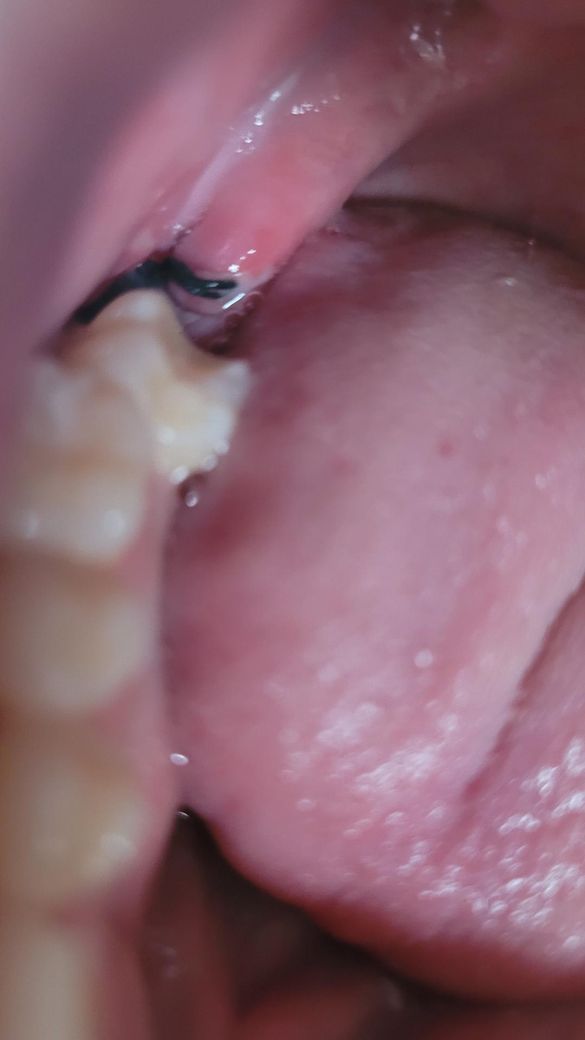

벽면이랑 실밥 있는곳이 이렇게 하얗게 올라왔는데 괜찮나요?

조금 입꼬리 올리면 아프고 혀로 건들면 아파요

제가 보기엔 잘 아물고 있는 것 같습니다. 입꼬리를 올릴 때 입안의 점막도 함께 움직이기 때문에 실밥이 당겨져서 가만히 있을 때보다 더 통증이 생길 수 있고, 상처가 아직 아물지 않았으니 당연히 건들면 아플 수 있습니다. 혀로 자꾸 만지면 자극이 되고 감염우려가 있으니 만지지 않는것이 좋습니다. 하얗게 생기는 것은 상처가 아무는 과정에서 생기는 것이라서 걱정하지 않으셔도 됩니다.

약간 염증 상태입니다 항생제 약 드시고 발치 부위 위생관리를 잘해주시면 됩니다 살살 가글해주세요